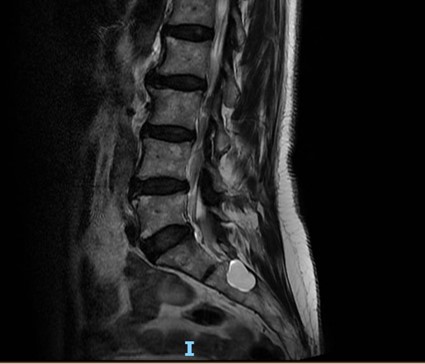

Tarlov cyst : an uncommon cause of perianal chronic pain

Doente com queixas de dor perianal crónica, incontinência fecal e urinária, bem como parestesias e diminuição da força muscular no membro inferior esquerdo. A Ressonância Magnética mostra quisto de Tarlov em S2.